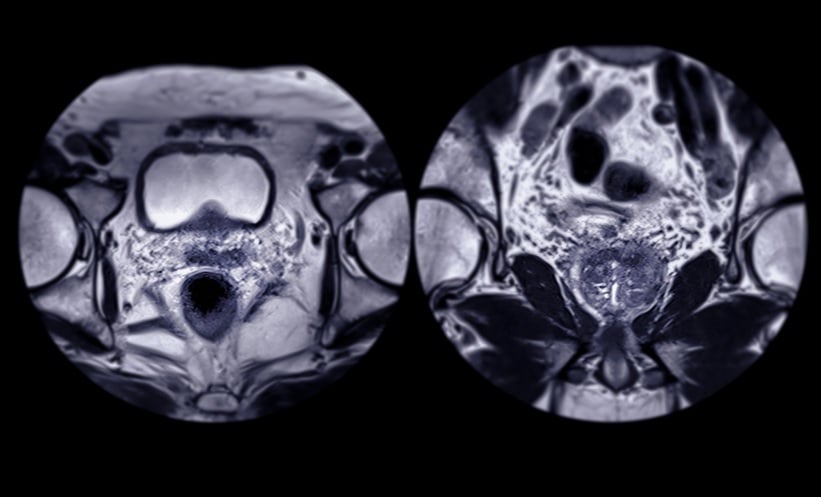

Between October 2011–March 2017, 1,432 patients undergoing radical prostatectomy were enrolled at a single centre. Surgeons were cluster randomised to perform either limited PLND (external iliac nodes) or extended PLND (external iliac, obturator, and hypogastric nodes), with crossover every three months. Cox proportional-hazards regression, with robust standard errors clustered by surgeon, was used to assess the impact of PLND template on BCR and metastasis rates. At a median follow-up of 4.2 years for BCR and 5.4 years for metastasis, the study confirmed comparable BCR rates between the two groups (hazard ratio [HR]: 1.05, 95% CI: 0.97-1.13; p=0.3). However, extended PLND demonstrated a significant protective effect against metastasis, with a 18% reduction in any metastasis (HR: 0.82, 95% CI: 0.71-0.93; p=0.003) and a 25% reduction in distant metastasis (HR: 0.75, 95% CI: 0.64-0.88; p<0.001).